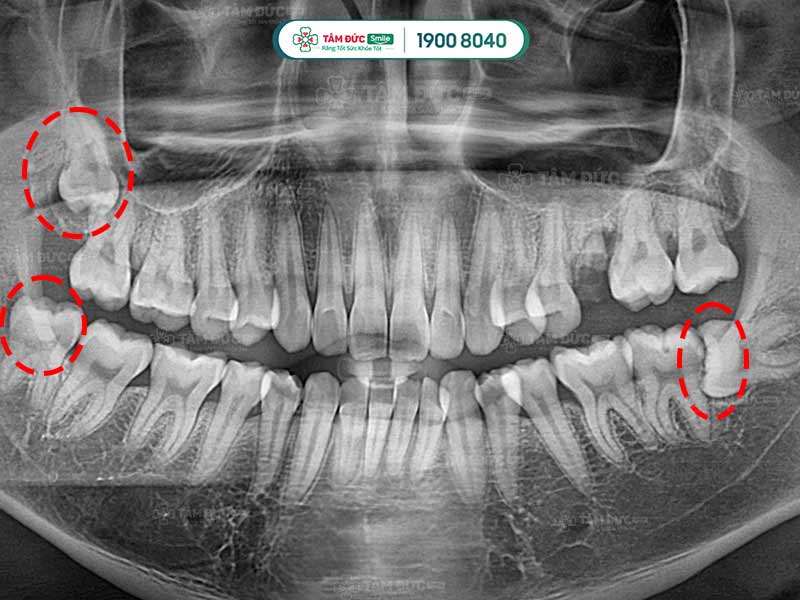

Quý khách có thể nhận biết răng khôn mọc ngầm thông qua phim chụp X-Quang

2. Cách nhận biết răng khôn đang mọc ngầm

Trước khi nhổ bỏ răng khôn mọc ngầm, Quý khách được bác sĩ chụp X-quang răng và thực hiện các xét nghiệm máu cần thiết. Qua phim X-Quang, bác sĩ biết được ảnh hưởng của răng đang mọc ngầm để cân nhắc phương pháp điều trị thích hợp nhất.